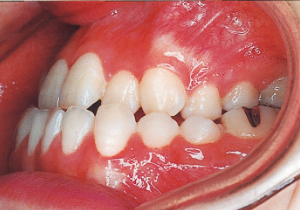

4 Initial Visit 8-29-’79

Although there were many missing deciduous teeth, the number of permanent teeth was not problematic (4). The amount of negative overjet was significant (1). On cephalometric radiographs, the mandibular ramus was not relatively long, but the large gonial angle and the long mandibular body were noticeable, indicating an overall tendency of the mandible to project inferiorly and anteriorly. High lower facial height was also characteristic.

A potential predisposition to mandibular protrusion was clearly evident.